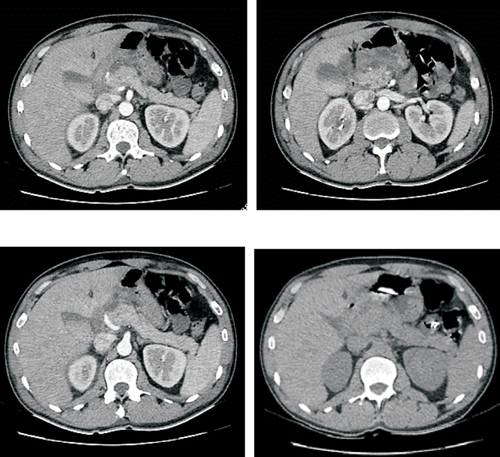

A las ocho horas posteriores al procedimiento de LEOC, instala vómitos incoercibles y dolor abdominal a predominio de hemiabdomen superior, sin fiebre. Se solicitó paraclínica de valoración general que evidenció hiperleucocitosis de 19.270 uL y amilasemia de 579 U/l; se le realizó una tomografía de abdomen que evidenció: alteraciones de la grasa peripancreática, escasa cantidad de líquido a nivel del espacio perigastroduodenal y escaso liquido libre intraabdominal; el sector cefalopancreático se observó levemente aumentado de tamaño con densidad heterogénea y se observó el catéter doble J normo posicionado a derecha. A las 48 horas, el paciente incrementó los síntomas de intolerancia digestiva, agregó distensión abdominal difusa e intensificó el dolor abdominal. En las siguientes horas instaló polipnea, taquicardia sinusal y fiebre. Se solicitó nueva paraclínica de la que se destaca una amilasemia de 1.047 U/l, proteína C reactiva (PCR) de 196 mg/l, hematocrito (HTO) de 48%, hiperleucocitosis de 21.300 µL, hiperazoemia 1,48 g/l con creatininemia de 2,24 mg/dl, funcional y enzimograma hepáticos normales. Se repitió la tomografía de abdomen que evidenció parénquima pancreático aumentado de tamaño a predominio cefálico, importante alteración de la grasa adyacente, menos de 30% de necrosis y una colección aguda peripancreática (figura 2). No se encontró evidencia de litiasis biliar ni dilatación de la vía biliar principal por ecografía ni por tomografía. El paciente se mantuvo lúcido, con elementos de síndrome de respuesta inflamatoria persistente (polipnea, taquicardia, fiebre e hiperleucitosis), presentó hipotensión arterial que fue transitoria. Durante las primeras 72 horas presentó elementos de disfunción gastrointestinal aguda grado 2, como ausencia de ruidos abdominales, vómitos persistentes y volumen residual gástrico aumentado, hipertensión intraabdominal (presión intraabdominal > o igual a 12 mmHg). El dolor se controló con opiáceos y antiinflamatorios no esteroideos; se realizó reposición de fluidos con cristaloides balanceados (suero ringer lactato) precozmente y dirigida por objetivos. Al cuarto día se inició nutrición enteral (NE) por vía yeyunal a través de una sonda naso yeyunal (SNY), con una fórmula enteral completa, polimérica, isocalórica, isonitrogenada y sin fibras (figura 3). El paciente no presentó elementos de intolerancia a la NE.

Figura 2: Tomografia de abdomen. Se observa la cabeza pancreática aumentada de tamaño, presenta contornos mal definidos y realce heterogéneo (< de 30% de necrosis). Cuerpo y cola de aspecto conservado. Leve dilatación difusa del conducto de Wirsung. Importante alteración de la grasa peripancreática en relación con el sector cefálico que se extiende al mesenterio adyacente y mesocolon transverso. Se identifica colección adyacente a la cabeza pancreática que acompaña las alteraciones de la grasa mesentérica, mide aproximadamente 60 mm cefalo-caudal y en el sector más voluminoso 35 mm T por 32 mm AP. Están engrosadas las fascias retroperitoneales, en particular a derecha, existiendo escasa cantidad de líquido en el espacio renal anterior. También se observa líquido libre en reducida cantidad en la gotera parietocólica derecha y en saco de Douglas.